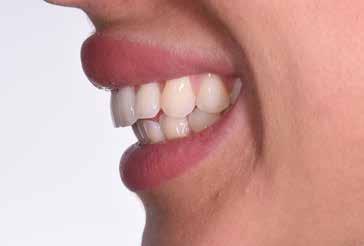

97 96 ESTETICA FUNZIONE POSTURA 145 _ Profilo sinistro con sorriso. 146 _ Ripresa di 3/4 sinistra con sorriso. 147 _ Immagine frontale naturale, senza sorriso. 148 _ Immagine frontale con sorriso. 149 _ Ripresa di 3/4 destra con sorriso. 150 _ Profilo destro (senza) con sorriso. 151 _ Dettaglio del sorriso. 152 _ Dettaglio del sorriso nel profilo destro. 153 _ Dettaglio del sorriso nel profilo sinistro.